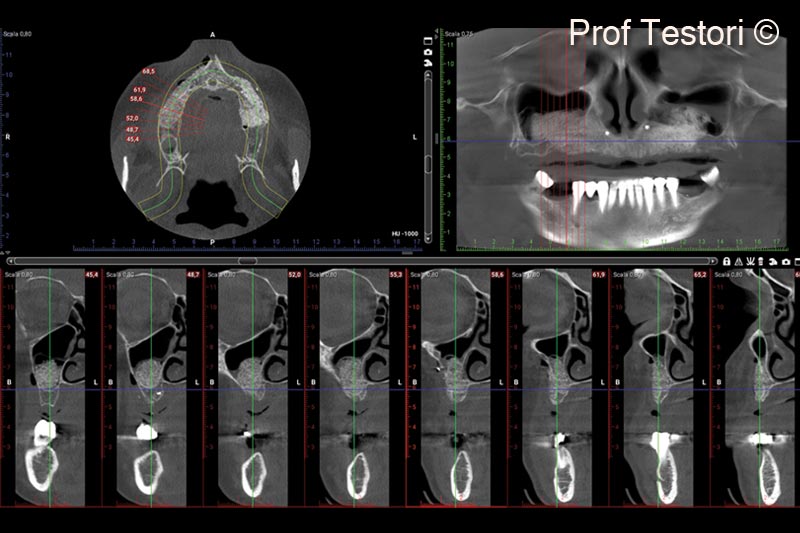

14. 10-months follow-up CBCT before implant uncovering

15. 10-months follow-up CBCT before implant uncovering